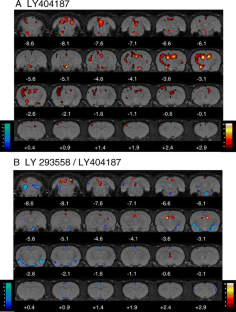

LY404187 produced significant increases in BOLD contrast in brain regions including the hippocampus, lateral and medial habenulae and superior and inferior colliculi. These changes were blocked by LY293558. When administered alone, LY293558 caused widespread decreases in BOLD contrast.

Fig. 1

Fig. 2

Fig. 3